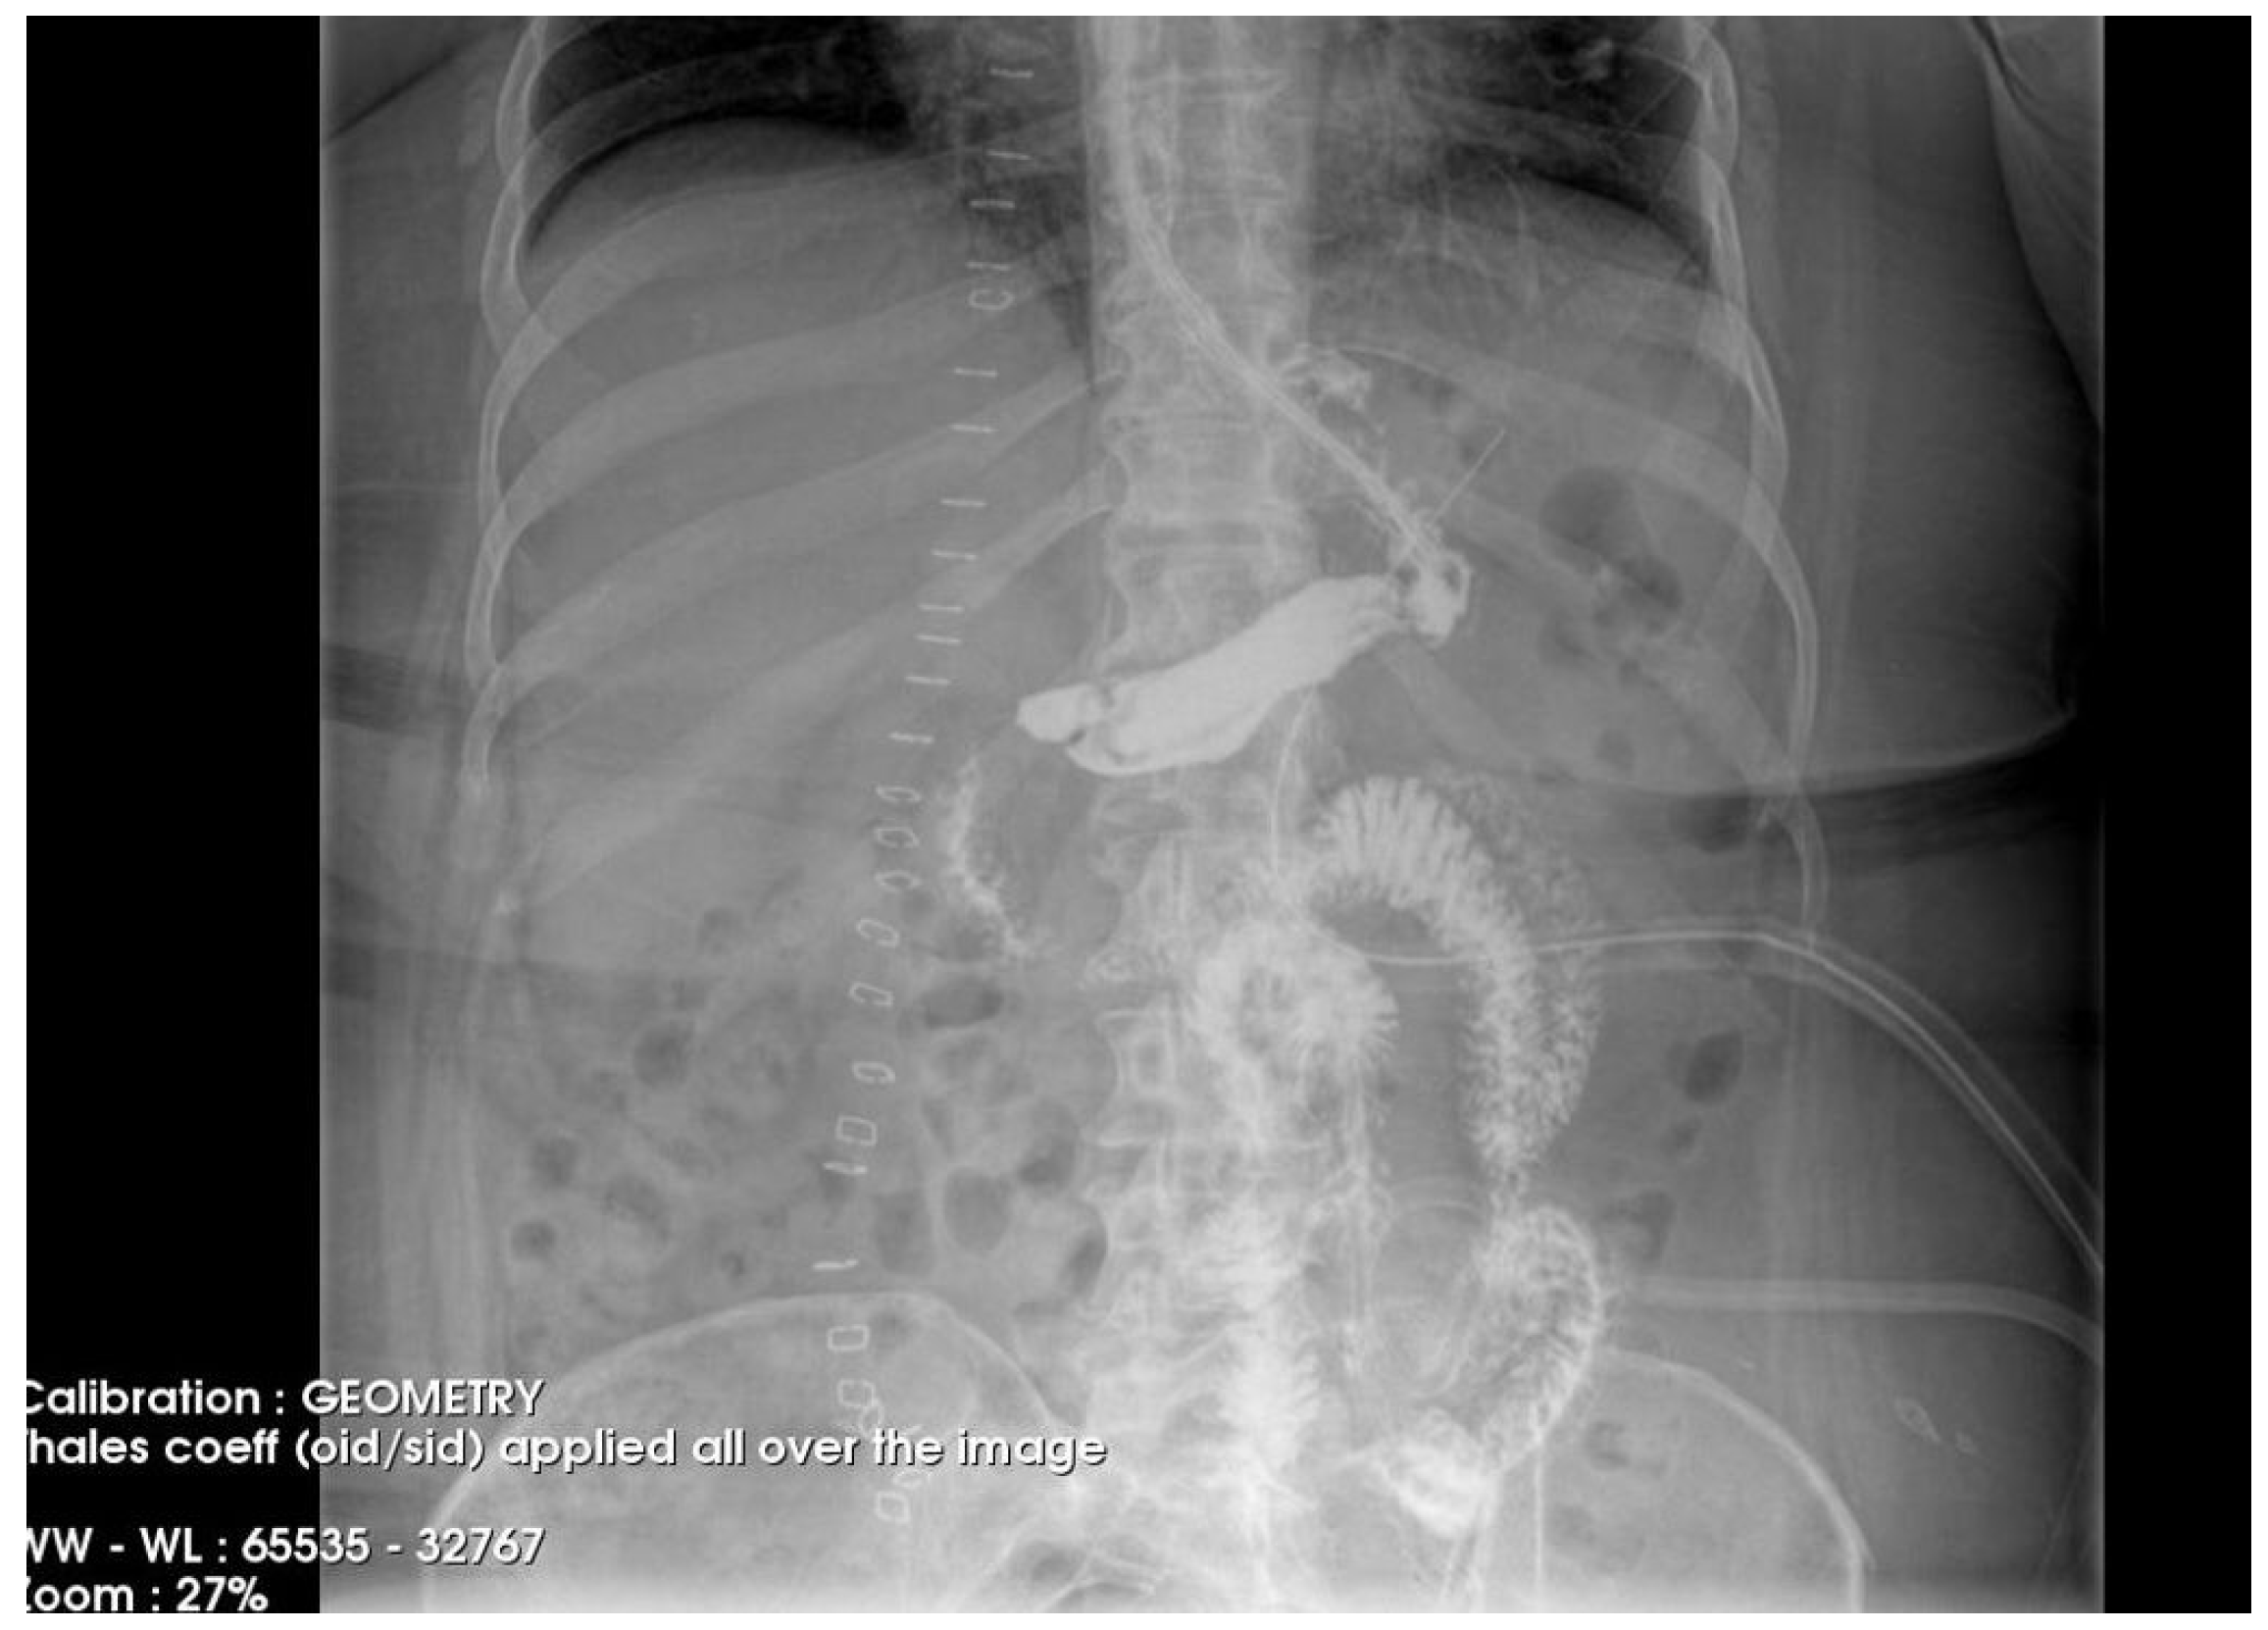

The postoperative course remained favorable (Figure 4 and Figure 5), allowing the medical team to discharge the patient after 51 days with specific recommendations.

Figure 4. Contrast-enhanced abdominal radiograph demonstrating complete resolution of the fistulous tract, with no contrast leakage or communication visible.